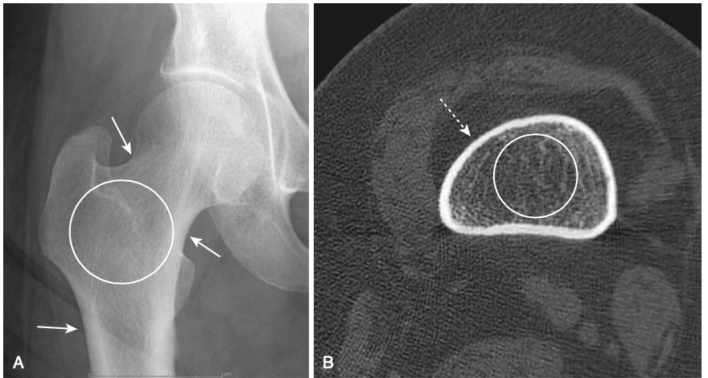

- Trên phim X quang thông thường, vùng hoại tử vô mạch xuất hiện đậm đặc hơn vùng xương xung quanh. Trên MRI, thường có sự giảm tín hiệu so với bình thường (cao) do tủy mỡ (Hình-6).

- Phần xương bị mất mạch máu trở nên đặc hơn và do đó có vẻ xơ cứng hơn phần xương còn lại. Điều này thấy rõ ở chỏm xương đùi (Hình-7) và chỏm xương cánh tay.